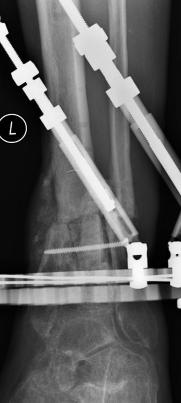

Postoperative (13th) images of left ankle

The image(s) displayed here were created following Liam's 13th surgery which was performed by Dr. Saunders. After a few hiccups getting

the surgery scheduled, Liam spent most of the September 13th afternoon in his 13th surgery. ;-) The surgery lasted about 5 hours and according

to the doctor, it was a good surgery. The 1st photo shows the new frame bracing that holds Liam's ankle together. The next series of photos show

various angles of the ankle and the rods that go from the frame into and through the left ankle. There was some concern that the swelling would

burst and allow for infection. Looks like we are now past that concern. Liam is still on antibiotics to ward of potential infection. The flesh

images show how the skin reacts to having the leg adjusted by the brace. The doctor has had to cut the skin to allow the rods to move freely.